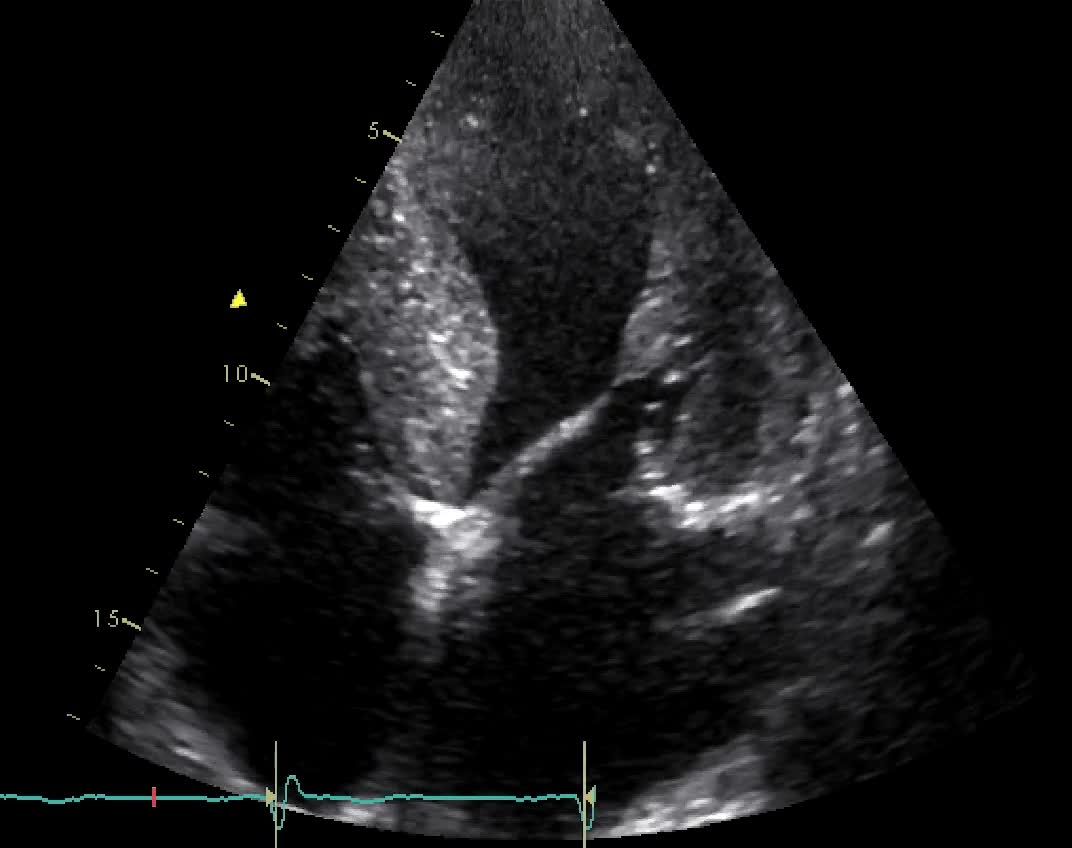

Non compattazione del VS

Autore:

Dario Sansalone

Santo Dellegrottaglie